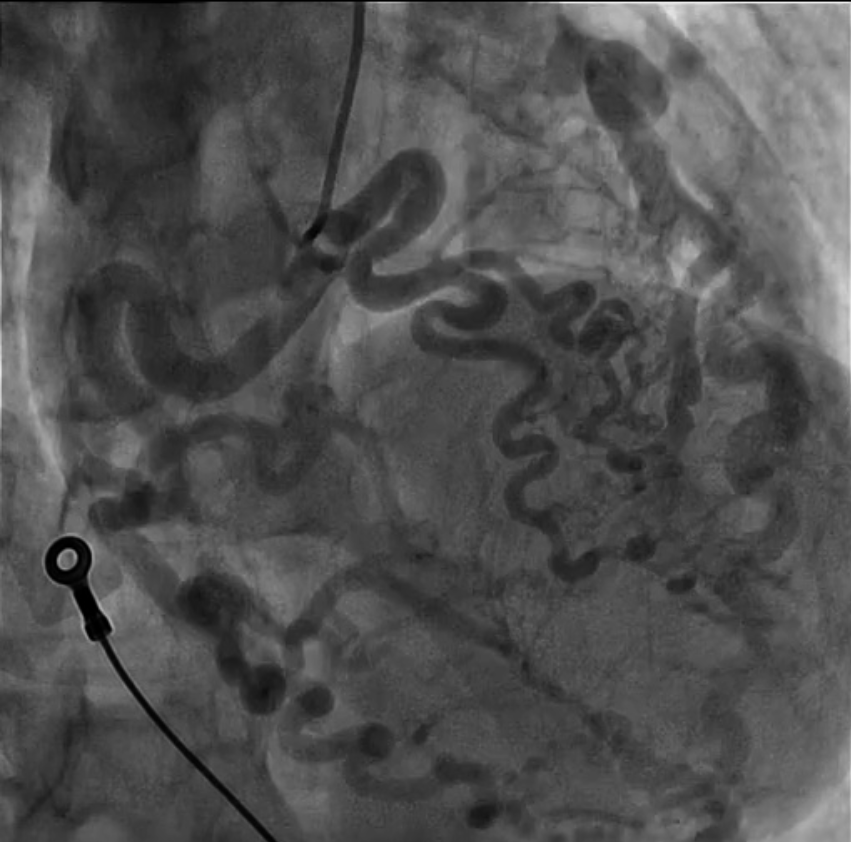

Background Out-of-hospital cardiac arrest is a major cause of mortality, most commonly related to ischemic heart disease. Rare congenital coronary anomalies may represent an uncommon but potentially lethal substrate for malignant ventricular arrhythmias. Case Presentation A 42-year-old woman with no known cardiovascular history was found unconscious in an out-of-hospital setting. On arrival of Emergency Medical Services, she was in cardiac arrest due to ventricular fibrillation. Electrical defibrillation restored spontaneous circulation(ROSC). Post-ROSC EKG showed a new-onset left bundle branch block. Urgent coronary angiography revealed a complex congenital coronary anomaly characterized by absence of the left main coronary artery and a single coronary artery arising from the right coronary sinus. The vessel appeared markedly ectatic and tortuous, giving rise to both the left anterior descending(LAD) and circumflex(LCx) arteries, without angiographically significant stenoses. Multiple coronary arteriovenous fistulas draining into the pulmonary artery and involving septal branches were also observed ( Image 1A ). Coronary CT confirmed the absence of the left main coronary artery and demonstrated a single ectatic coronary artery (up to 7 mm) originating from the right coronary sinus, with a highly tortuous course and formation of a vascular network at the cardiac apex. Retrograde filling of a dilated LAD and origin of a dilated LCx (7–8 mm) were observed ( Image 1B-C ). Multiple fistulous connections with hypertrophic bronchial arteries were present. A right-sided pneumothorax and pneumomediastinum were also detected and successfully treated with chest drainage. After a few days in the intensive care unit, the patient was weaned from mechanical ventilation with complete neurological recovery. Initial transthoracic echocardiography showed severe left ventricular systolic dysfunction (LVEF 30–35%), which improved to 60% during hospitalization. Given the occurrence of ventricular fibrillation in the absence of a reversible ischemic cause, a dual-chamber implantable cardioverter-defibrillator was implanted for secondary prevention. At discharge, the patient was prescribed only a beta-blocker. Conclusion This case highlights a rare presentation of complex congenital coronary artery anomaly with extensive coronary fistulization leading to sudden cardiac arrest. Advanced imaging and multidisciplinary management were essential for diagnosis and favorable outcome.